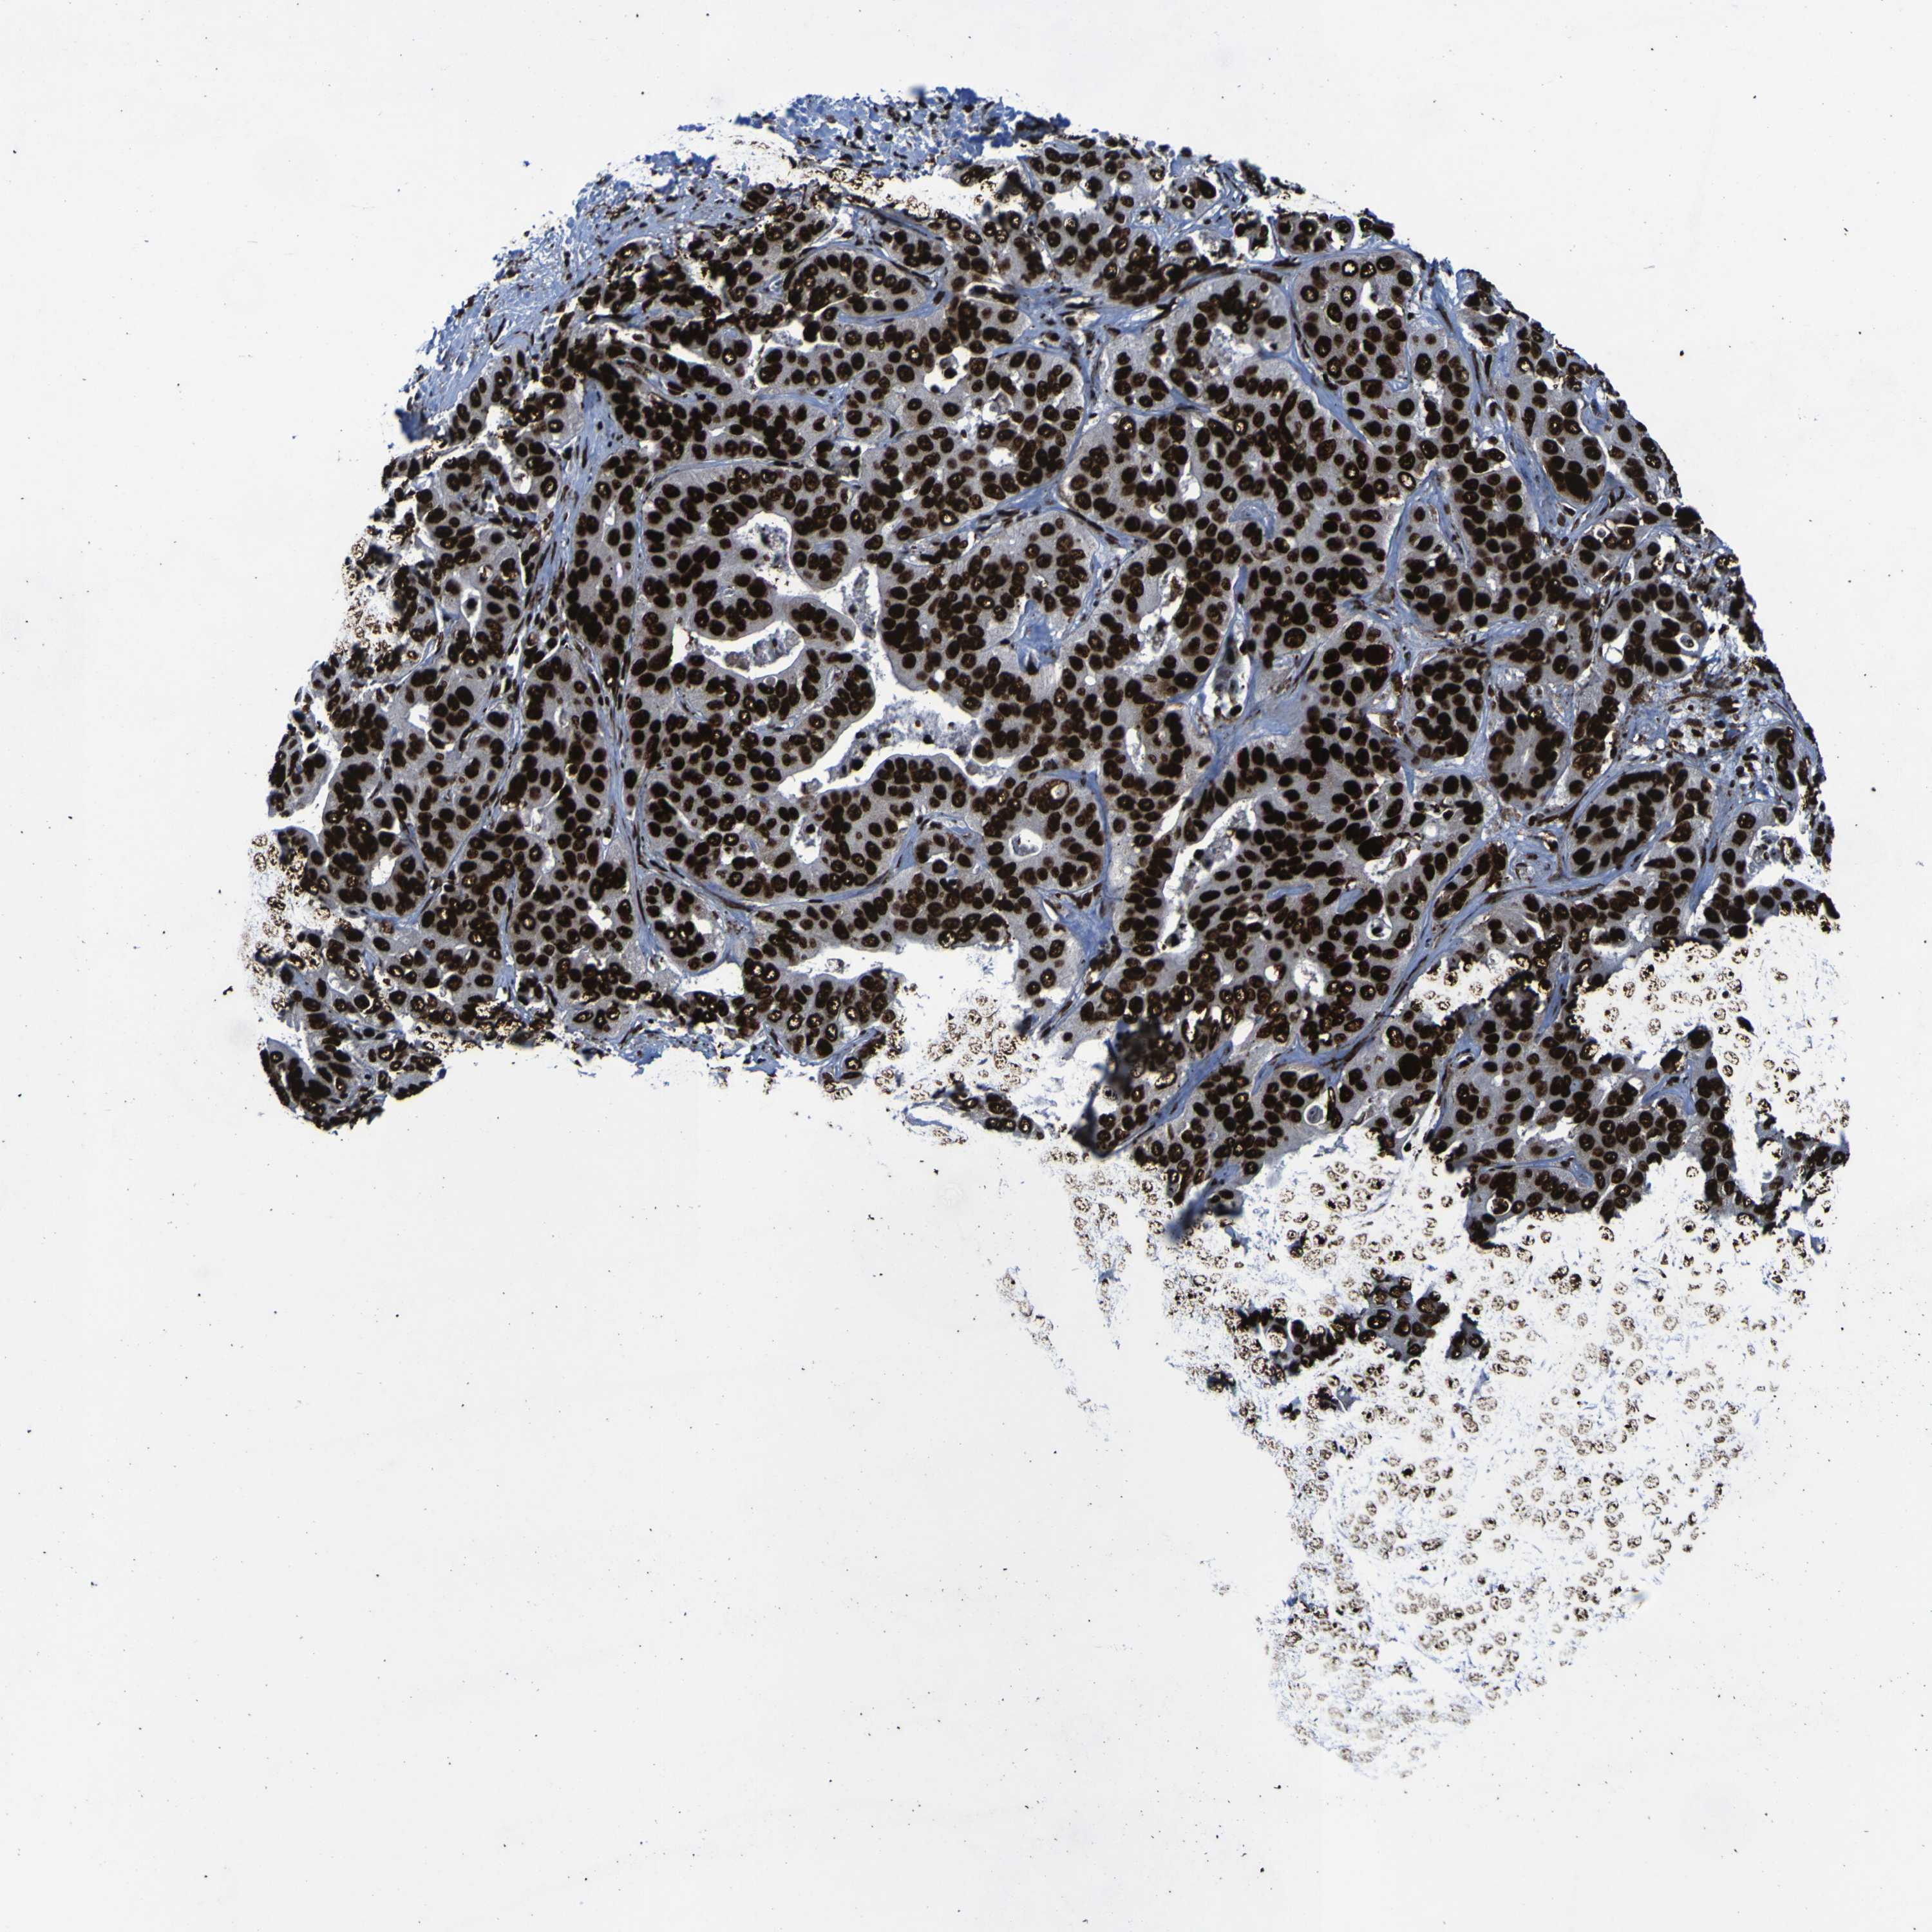

LIVER CANCER - Protein expressioni

A mouse-over function shows sample information and annotation data. Click on an image to view it in a full screen mode. Samples can be filtered based on level of antibody staining by selecting one or several of the following categories: high, medium, low and not detected. The assay and annotation is described here.

Antibody stainingi

Antibody staining in the annotated cell types in the current human tissue is reported as not detected, low, medium, or high, based on conventional immunohistochemistry profiling in selected tissues. This score is based on the combination of the staining intensity and fraction of stained cells.

Each image is clickable and will lead to virtual microscopy that enables deeper exploration of all samples and also displays staining intensity scores, fraction scores and subcellular localization as well as patient and tissue information for each sample.

Antibody HPA011384

Antibody CAB012983

Staining

High

Medium

Low

Not detected

Intensity

Strong

Moderate

Weak

Negative

Quantity

>75%

75%-25%

<25%

None

Location

Nuclear

Cytoplasmic/membranous

Cytoplasmic/membranous,nuclear

Cholangiocarcinoma

Carcinoma, Hepatocellular, NOS